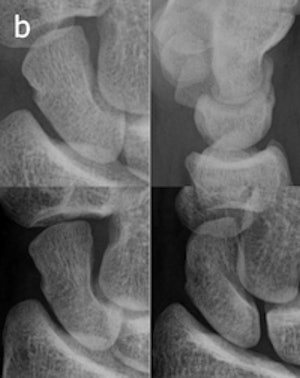

In the study, digital radiography was performed in the emergency department on 36 consecutive patients at the time of injury with pixel spacing of 0.1 mm. Posteroanterior (PA) and lateral views were captured. Coned-down special scaphoid views were obtained with the hand in ulnar deviation and the wrist in a slight pronation and supination, respectively, to obtain views of the proximal and distal half of the scaphoid with the x-rays perpendicular to the long axis of the bone.

The CR protocol was identical to the previous ER imaging routine. For tomosynthesis, 60 low-dose projection images were used to reconstruct tomographic sections with 1-mm nominal thickness without overlap, with a pixel spacing of 0.2 mm. The detector was stationary, while the x-ray tube was moved continuously from -17.5° to +17.5° around the standard PA position.

The experience also taught the participating radiologists that detecting fractures with tomosynthesis is somewhat different than with conventional radiography and CT. Fracture detection is mainly based on edge disruption with tomosynthesis because the structure of the medullary bone is blurred and not as distinct as in CT, Geijer noted.

The tomosynthesis sections had a "nonprecise" thickness, with a sharp resolution at the image center, and increasing "fuzziness" apparent toward the image edges.

Fracture detection was aided on the lateral borders by the ability to visualize the scaphoid bone cortex. Fractures could also be appreciated on the most dorsal and palmar sections because of good contrast between the bone and surrounding soft tissue or medullary bone, he wrote.

Image artifacts with tomosynthesis included increased noise during scaphoid imaging and the superimposition of adjacent cortical lines and carpal joint structures.

"The way a fracture is seen with tomosynthesis is thus different from both radiography and CT," he wrote.